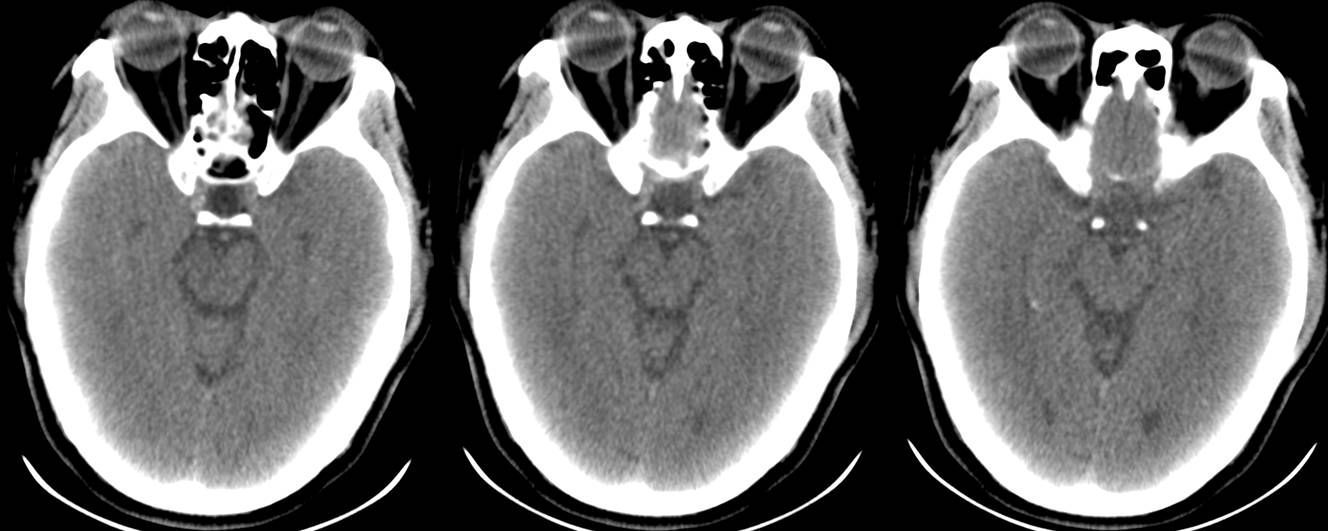

救护车载移动CT陈旧性脑梗塞扫描

救护车载移动CT扫描脑出血后软化灶形成